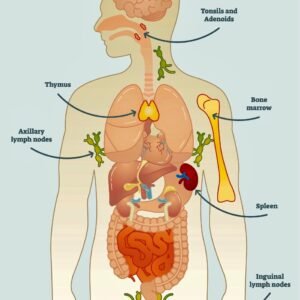

AIDS (Acquired Immune Deficiency Syndrome; HIV; VAIDS)